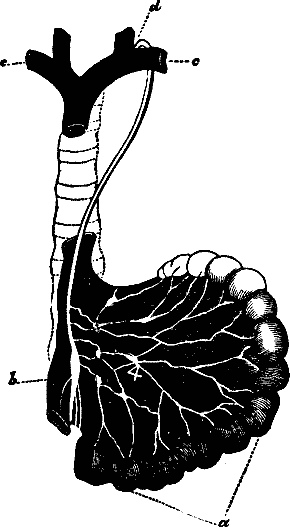

Fig. 32. c, c.

Right and left subclavian veins. b. Inferior vena cava. a.

Intestines. d. Entrance of the thoracic duct into the left

subclavian vein. 4. Mesenteric glands, through which the lacteals

pass to the thoracic duct.